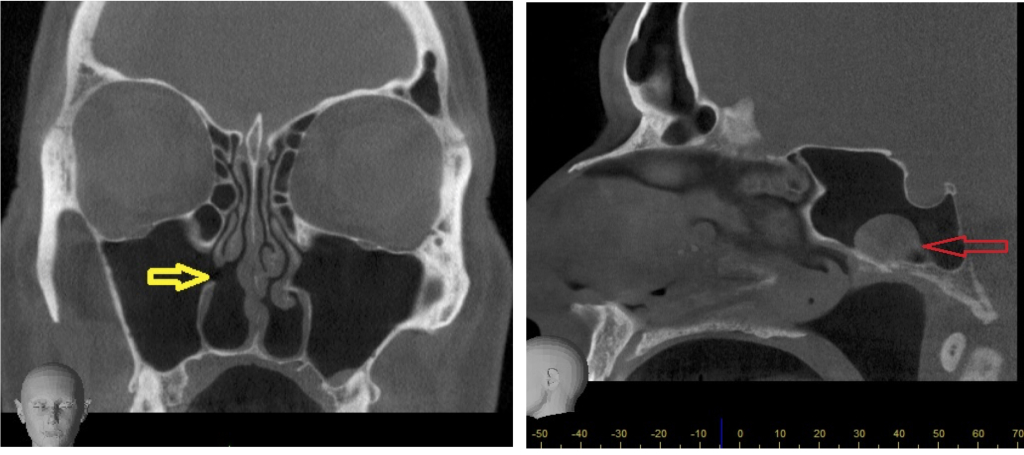

CBCT Paranasal Case Studies | Cavendish Imaging

CBCT Paranasal Case Studies | Cavendish Imaging www.cavendishimaging.com

sinus cbct case ostium accessory paranasal cyst sphenoid retention study turbinate left wall antral studies medial